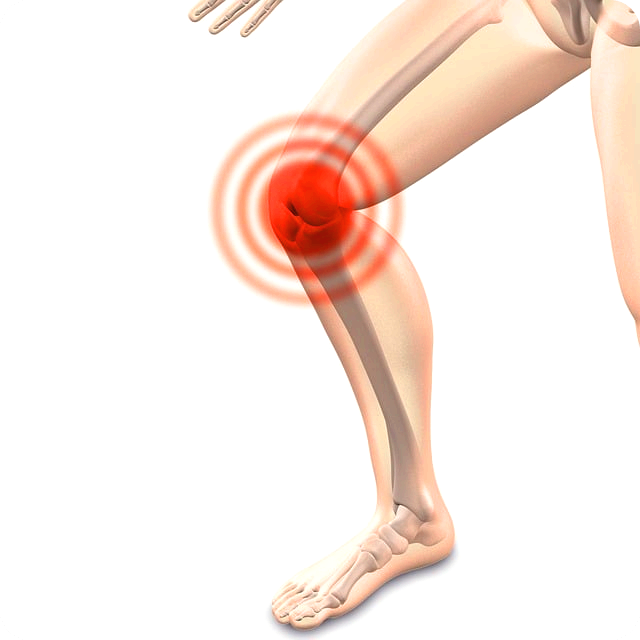

관절염은 많은 사람들에게 익숙한 질병 중 하나입니다.

이 질병은 관절 주변의 염증과 통증을 유발하여 일상생활에 불편함을 초래할 수 있습니다.

관절염은 관절 주변의 염증을 포함하는 질병의 그룹을 나타냅니다.

이 질병은 수많은 다양한 형태와 원인을 가질 수 있으며, 공통적으로 관절 부위에서 통증, 염증, 부종, 운동 제한 등의

증상을 유발합니다. 가장 흔한 관절염 형태로 류마티스 관절염, 골관절염, 골다공증, 강직성 척추염, 화농성 관절염 등이

있습니다.